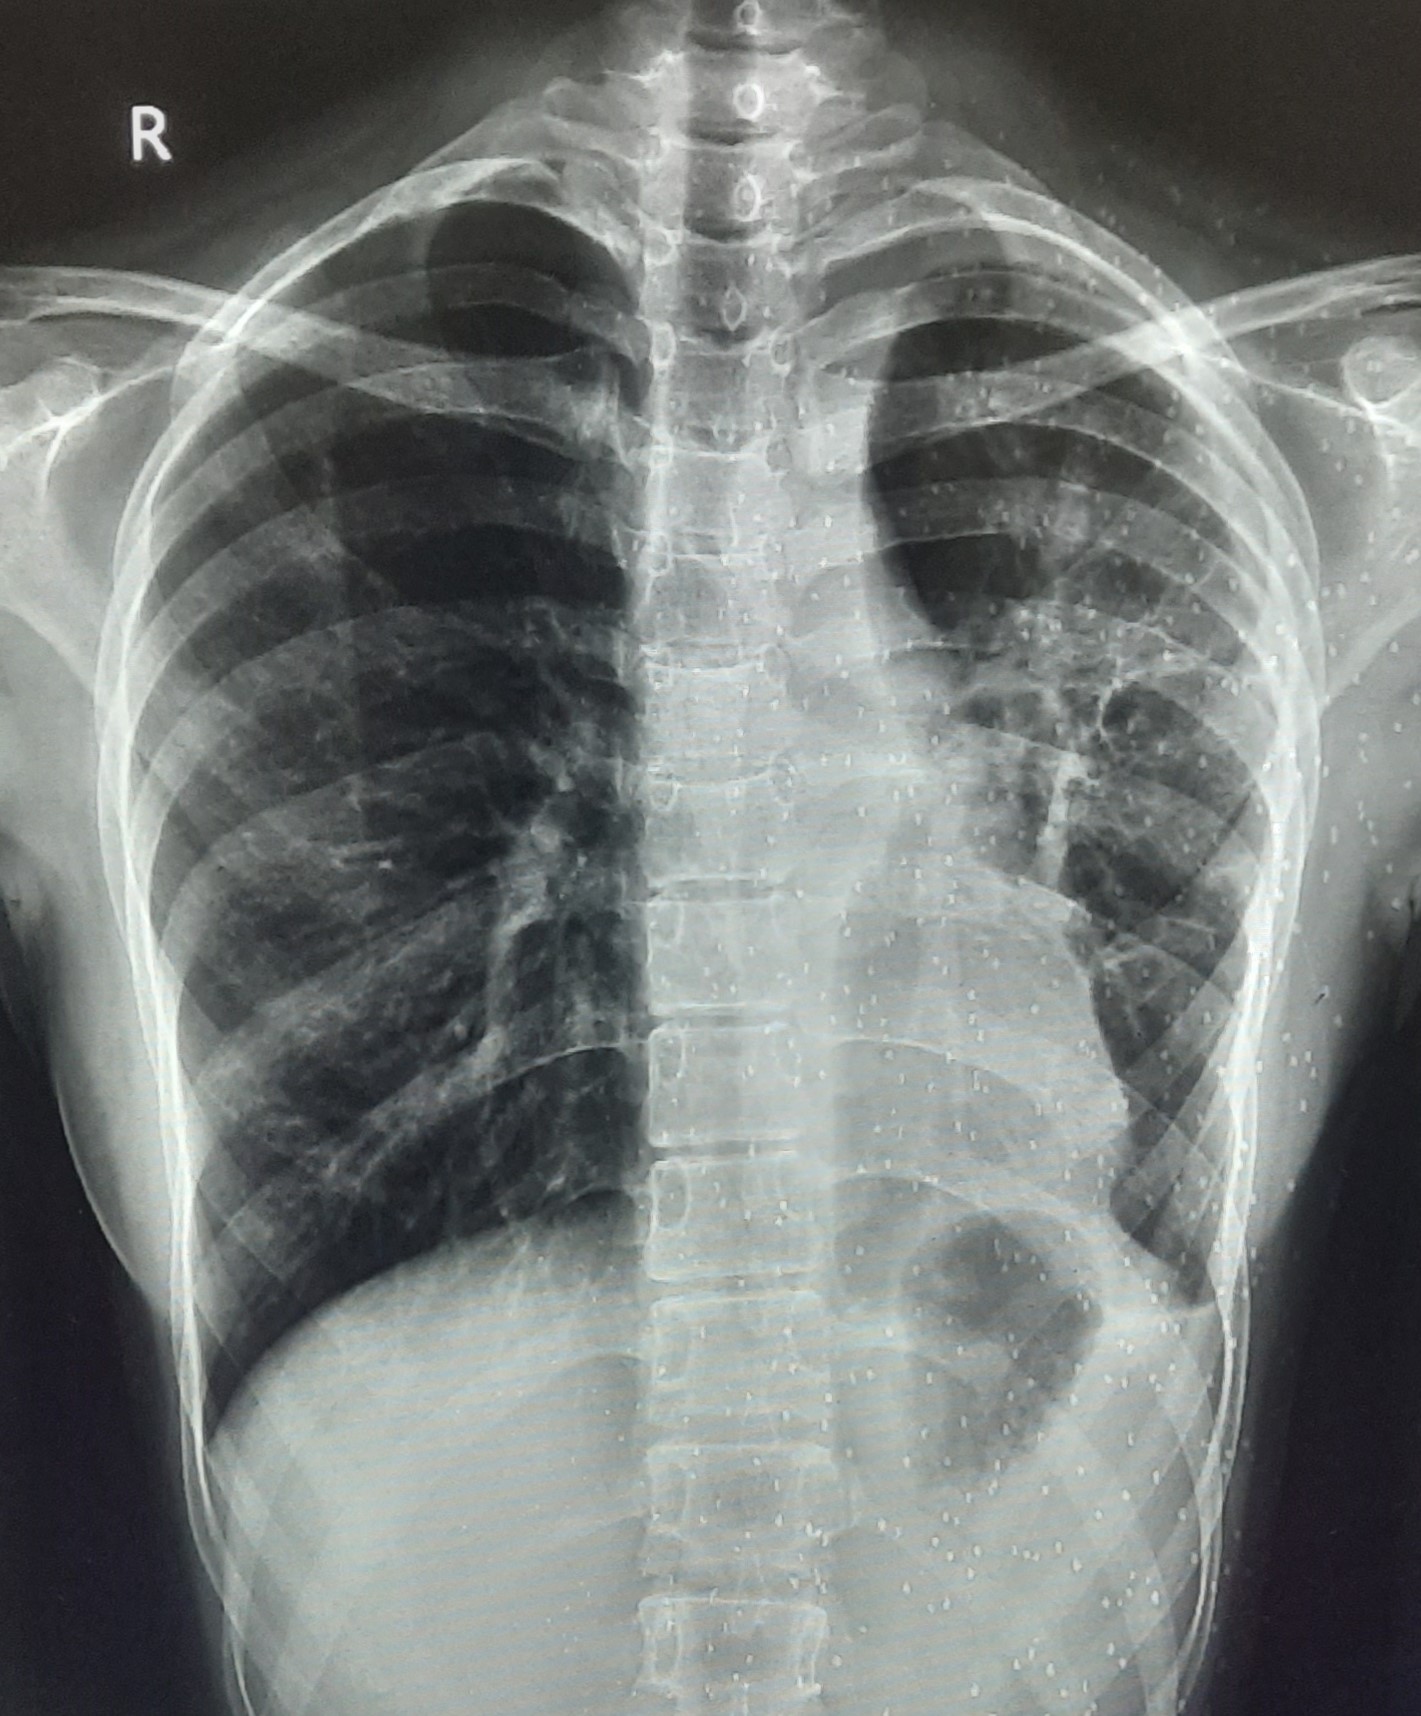

| 219 | IGGMC, Nagpur, Nagpur | P2 | 29-4253 | BACCHO CHAUDHARI | Consent taken on Paper | 47 Yrs. |

Provisional Diag : MILLIARY TB

Final Diag : BILATERAL INFILTRATION WITH MILLIARY SHADOWS |

TB Case (Confirmed) | BILATERAL INFILTRATION WITH MILLIARY SHADOWS | Abnormality visible on x-ray |

View |

|||